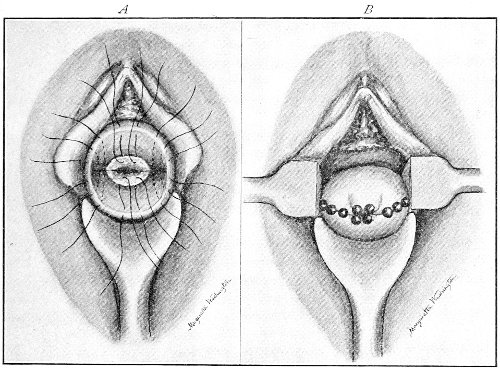

The injuries to the perineum that may result from childbirth are classified according to the position or the direction and extent of the laceration. They are as follows: slight median tear; median tear involving the sphincter ani; tear in one or both of the vaginal sulci; subcutaneous laceration of the muscles and fascia.

All these injuries demand operative treatment. The operation for the repair of injuries to the perineum is called perineorrhaphy. It is called immediate or primary, intermediate, and secondary perineorrhaphy, according to the time after the receipt of the injury at which the operation is performed. The primary operation is done during the first twenty-four hours. The primary operation should always be performed. A careful inspection of the perineum and the posterior vaginal wall should always be made after labor, and any laceration should be repaired within twenty-four hours. The advantages of the primary operation are many. The parts are usually so numb that it is not necessary to administer an anesthetic. No denudation is necessary, and therefore no tissue need be sacrificed. The woman is spared the pain and discomfort of granulation and cicatrization.

The bad results that follow neglect of the primary operation are very numerous, and will be studied hereafter. The injured muscles retract, and, being functionally useless, undergo atrophy, and when finally repaired never possess their former strength. Involution in the vagina and the uterus may be arrested, and all the disasters incident to subinvolution may appear. Vaginal and uterine prolapse occur; the natural supports of the 63 vagina and uterus become stretched, and, though afterward the perineum may be restored, yet it may be found impossible to retain the uterus in its proper position. It is always good surgery to repair an injury as soon as possible.

When practicable, a certain amount of preparation of the patient should be made before the operation of perineorrhaphy. This is most easily effected before the intermediate and secondary operations. The vagina and the vulva should be sterilized, and the intestinal tract should be emptied. Thorough evacuation of the bowels is most important when the sphincter ani has been injured, because it is desirable, after operation for this lesion, that the bowels should not be moved for five or six days. A saline purgative should be administered on an empty stomach about five hours before the operation, and a rectal injection of soap and water should be administered about one hour before the operation. Whatever purgative be employed, it should be administered at such a time that its action shall have ceased by the time of the operation. If this precaution is not observed, there may be a discharge of feces that will infect the wound and interfere with the manipulations.

For operation upon the perineum the woman should be placed in the dorso-sacral position (Fig. 1, page 23).

The intermediate operation is performed during the granulation period—ten days or two weeks after labor. At this time the raw surfaces are covered with granulation-tissue and bathed with pus. The edges of the wound and the surrounding tissue may be hard and swollen from infiltration with inflammatory products. In the intermediate operation it is necessary to administer an anesthetic or to anesthetize the parts locally with a 10 per cent. solution of cocaine.

All cicatricial tissue, granulation-tissue, and rough edges should be scraped away with the knife, the scissors, or the curet. The raw surfaces should be thoroughly 64 washed with a 50 per cent. solution of peroxide of hydrogen and a 1:1000 solution of bichloride of mercury. The sutures should then be introduced.

The secondary operation is performed at any time after cicatrization has occurred—often many years after the receipt of the injury. This operation is at present one of the commonest in gynecology, because the injury is not detected, is neglected, or is improperly repaired after labor. In the secondary operation an anesthetic is necessary. The mucous membrane must be removed or denuded on the posterior wall and about the mouth of the vagina, in order that the lacerated structures may be brought again in apposition. The denudation is best made by means of scissors curved on the flat (Figs. 24 and 25).

The strip of mucous membrane to be removed is picked up with a tenaculum (Fig. 26) or with tissue forceps 65 (Fig. 27); the scissors are placed with the blades parallel to the surface to be denuded, and the strip is cut away evenly, in one piece if possible. A similar contiguous strip is removed, and so on until the necessary surface is bare. Sponges in holders (Fig. 28) or continuous irrigation may be used to remove blood.

Silver wire and silkworm gut are the best sutures in the operation of perineorrhaphy.

The sutures may be fastened by passing the ends through a perforated shot which is slipped down to the line of union and compressed by the shot-compressor (Fig. 32). All blood should be carefully removed from the surfaces that are brought together. The sutures should only be sufficiently tense to produce accurate apposition. A light gauze drain should be introduced in the vagina, and should be removed in forty-eight hours. Afterward one vaginal douche of about a quart of warm bichloride solution (1:2000) should be administered every day. After the douche the labia should be separated and the vagina carefully dried by cotton held in dressing-forceps. Except in those cases in which the sphincter ani is involved, the bowels may be moved on the second or third day. The woman should stay in bed for two weeks, at the end of which time the sutures should be removed. 67 She should avoid heavy lifting, long standing, and bicycle- or horseback-riding for two months after the operation. Constipation should always be avoided. Coitus may be resumed six weeks after operation.